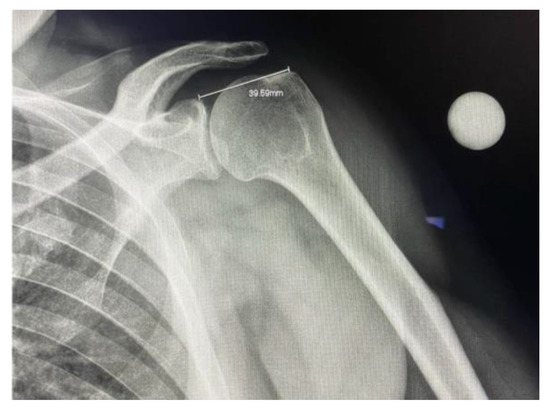

A true anterior-posterior view of the glenohumeral joint was used for the evaluation. Thus, the subject’s scapula on the imaged side was laid flush against the image detector. As a result, the subject’s thorax was rotated toward the affected shoulder at 30–45°. (Figure 1).

To ensure standardization, the X-ray tube was positioned at 20° caudal angulation centered at the glenohumeral joint. The superior glenoid and greater tuberosity were used as reference landmarks for measurement and quality of the image. A radiographic reference ball was placed at the level of the coracoid process, in contact with the subject’s skin.

After capturing the plain film radiograph, the raters were instructed to calibrate the system using the radiographic reference ball. Using the calibration measurement tool, a straight line was drawn through the diameter of the ball, and a real length value of 25 mm was entered manually. Upon calibration, the ruler device was used to place a marker at the superior aspect of the glenoid where the medial anchors would be placed and another at the greater tuberosity where the lateral anchors would be placed. The distance would then be generated. (Figure 2).

Figure 2. Plain film radiograph of the glenohumeral joint with a measurement of the distance between the superior glenoid and the insertion point of supraspinatus.